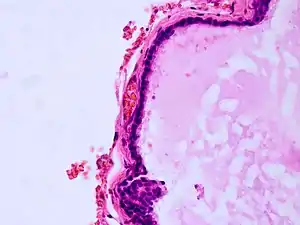

| Histopathology of colloid cyst |

A colloid cyst is a non-malignant tumor in the brain. It consists of a gelatinous material contained within a membrane of epithelial tissue. It is almost always found just posterior to the foramen of Monro in the anterior aspect of the third ventricle, originating from the roof of the ventricle. Because of its location, it can cause obstructive hydrocephalus and increased intracranial pressure. Colloid cysts represent 0.5–1.0% of intracranial tumors.[1]